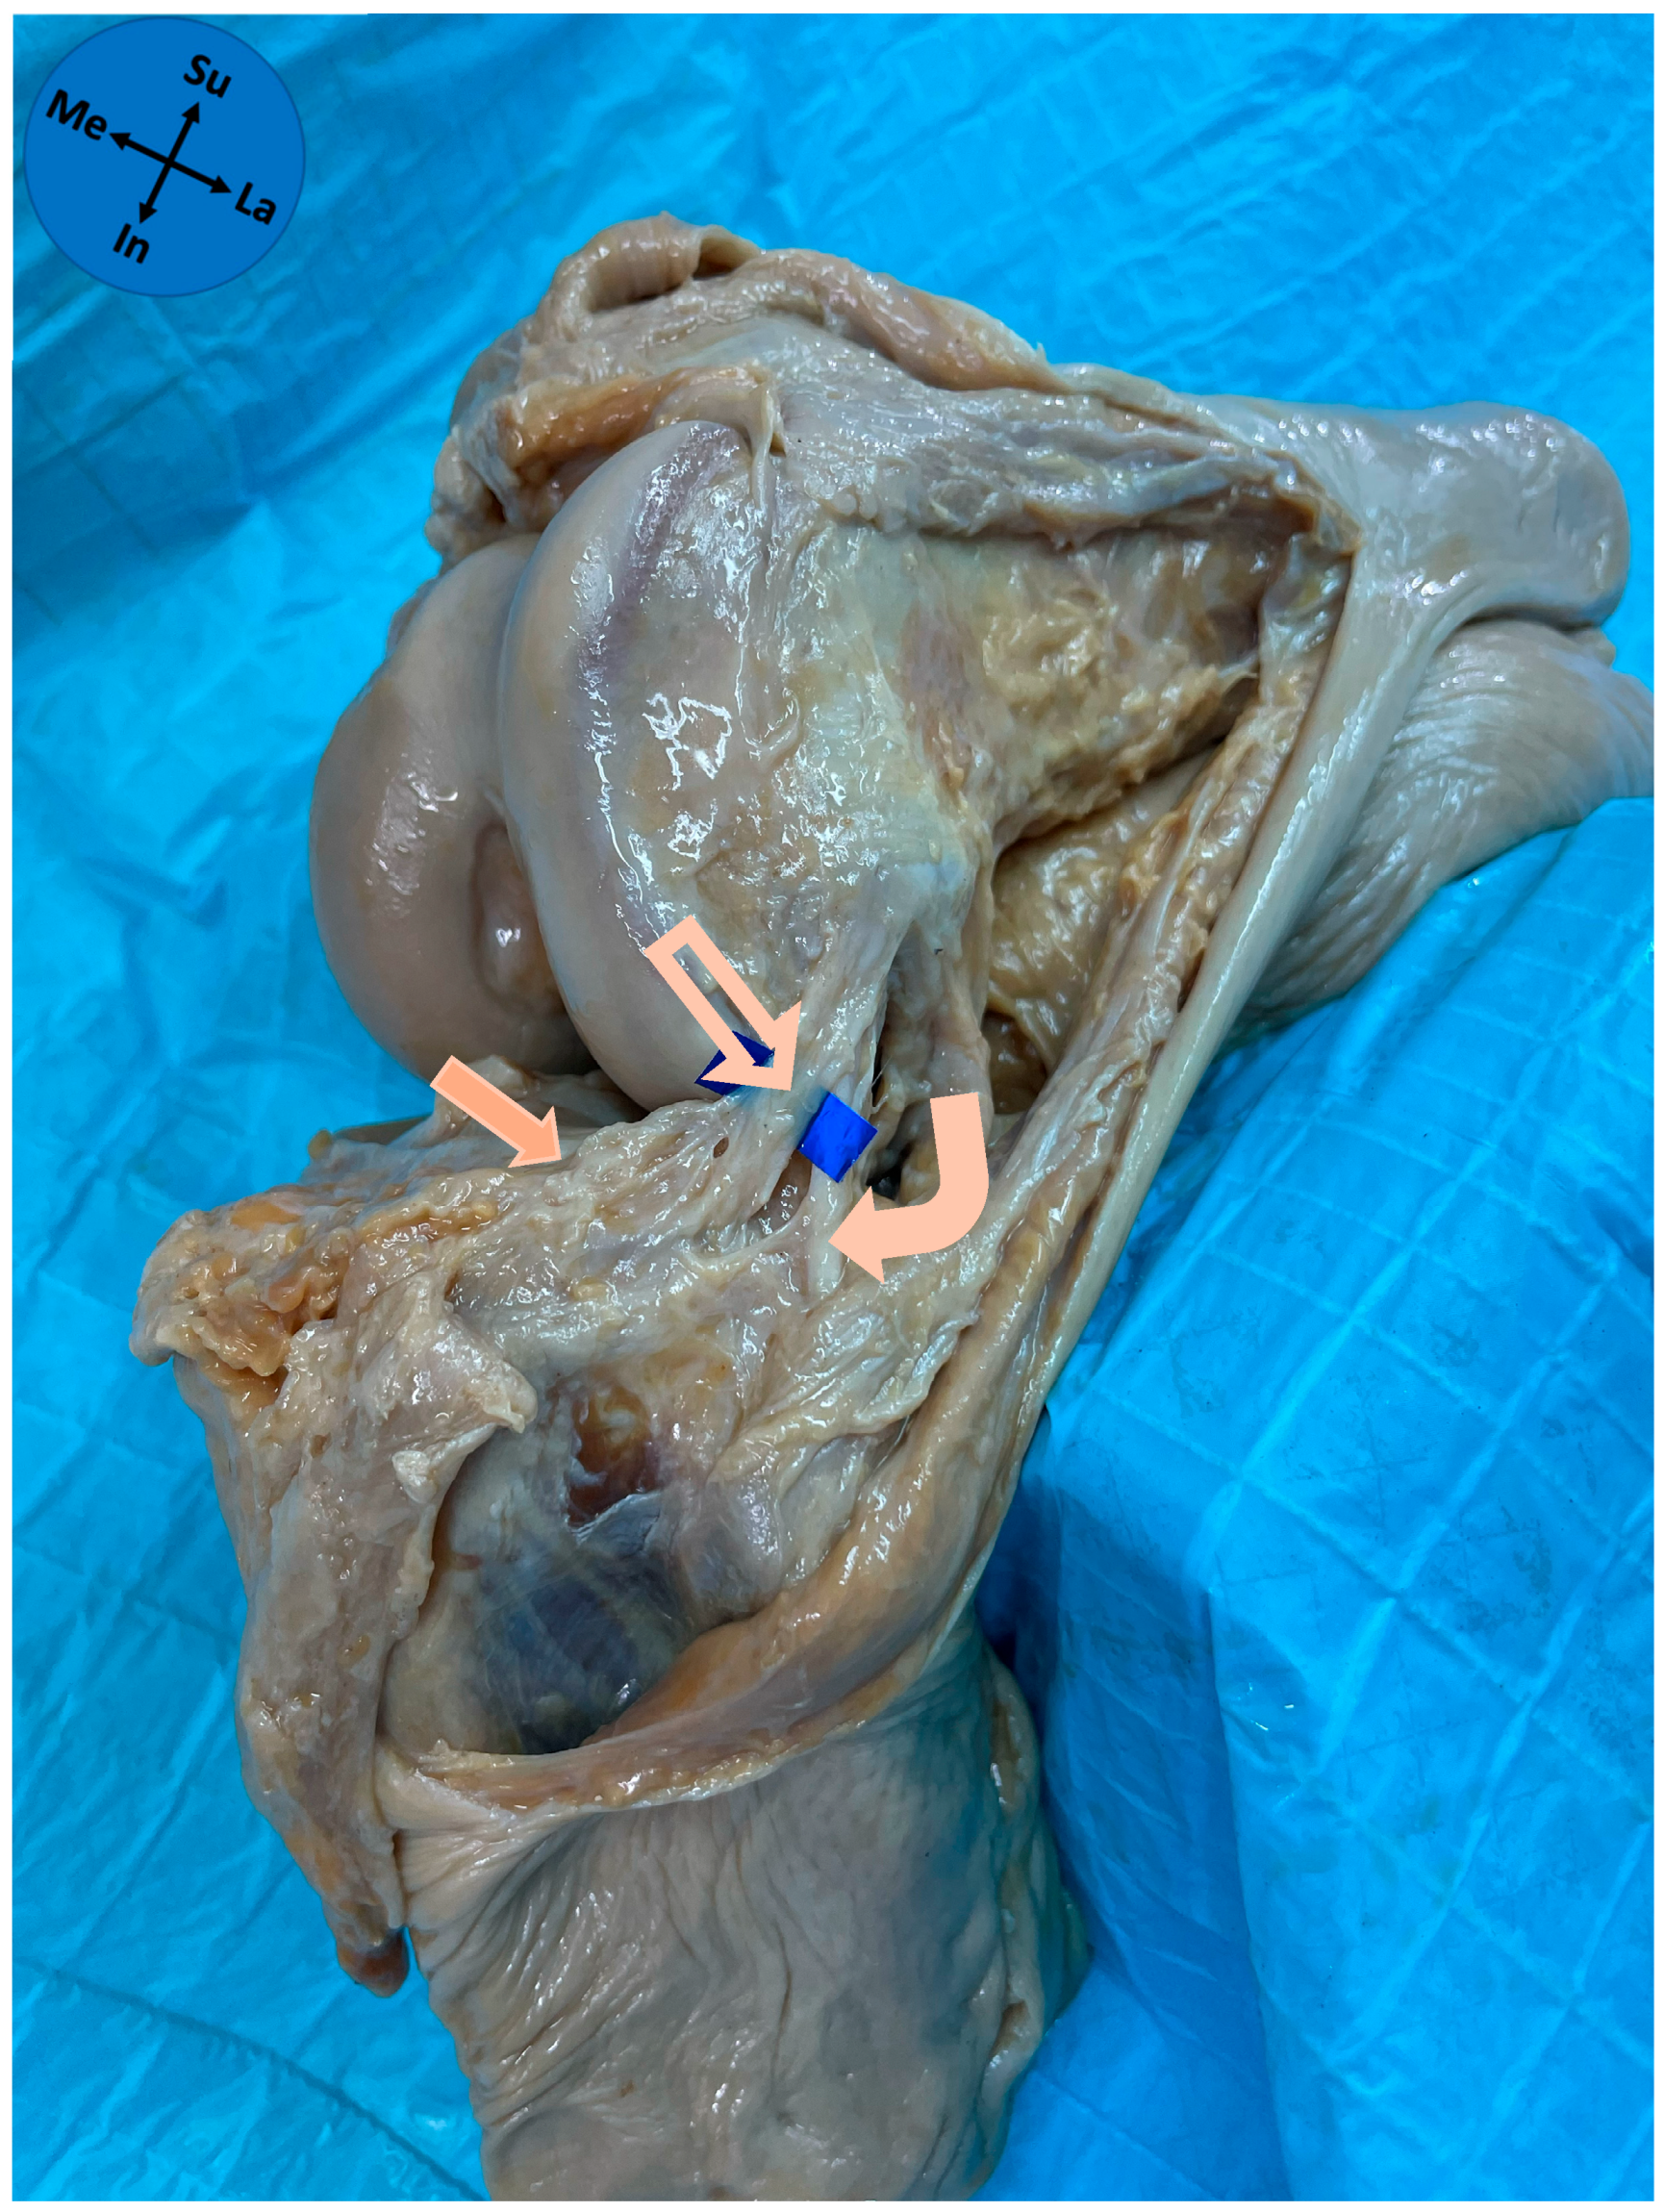

| Meniscal Zone of Attachment | n (%) |

|---|---|

| Zone 2a | 1 (3.2) |

| Zone 2b | 30 (96.8) |

| Pattern of meniscal attachment | n (%) |

| Full thickness | 13 (41.9) |

| Bipolar | 11 (35.5) |

| Superior-only | 4 (12.9) |

| Inferior-only | 3 (9.7) |